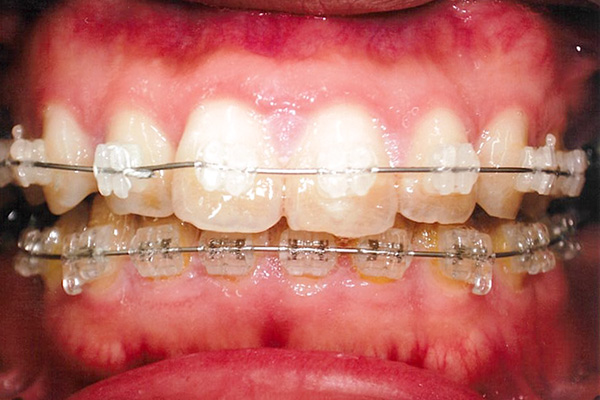

24ヶ月後

| 症状 | 下顎第一大臼歯の欠損 |

| 想定されるデメリット | 臼歯の近心移動が非常に難しい。高度なテクニックが必要である。 3D-LST矯正治療法を用い、抜歯を最小限に抑えながら歯の近心移動を実施。 |